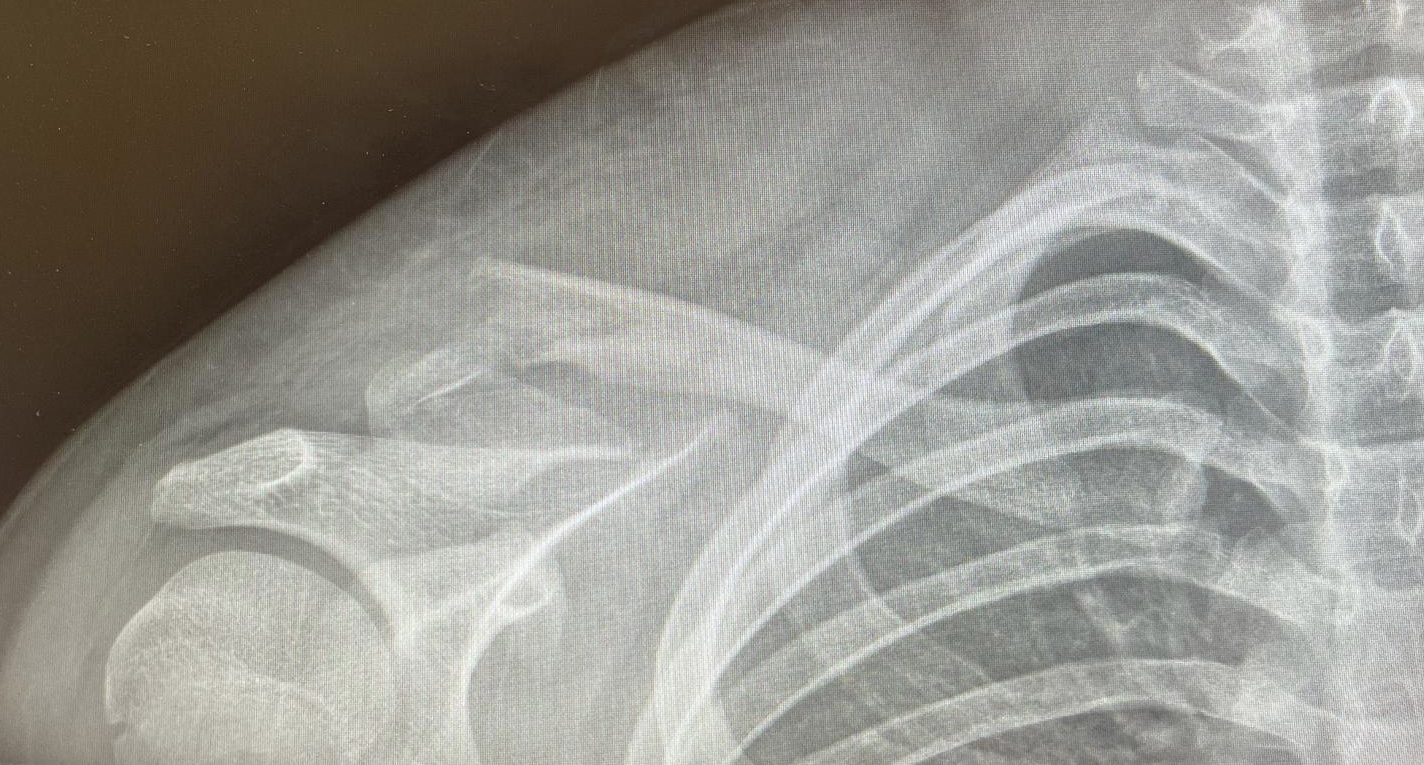

We then suffered the first injury of the trip with my son falling and fracturing his clavicle. The health and safety plan kicked in and he had both a shoulder surgical opinion followed by a paediatric surgeon opinion in short succession. Meyer was a DOC ranger on the track for many years and guided us to the road which was luckily only 800m away where he was swiftly picked up and transported to the shuttle hub for analgesia. The PLB stayed unused fortunately. He is doing well with conservative management.

After watching the planning for the Wishbone Relay from the side, it was great to finally take part in one of the legs. What a great couple of days we had on the Timber Trail! Not only was the scenery and track stunning, and the effort exhausting, the opportunity to share the experience with a group of colleagues was a special feature of the weekend. It made me realise an unexpected value of this event, bringing members of our association from different regions together to experience an event not focused on our day to day work. Equally to share this experience with some of the industry sponsors away from work or typical conferences was another highlight. Clearly this was part of the direction Perry and Ian wanted the Relay to follow and my thanks to all involved in the organization. From the highs and lows of the weather to the highs and lows of the cycling effort, not a negative word was heard all weekend. I’m sure the end was a bit of a low for Joe Galley with his injury, but he bore that with the mark of a trouper and will ride again soon.